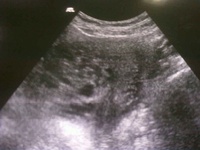

Gravidez molar

Ultrassonografia mostrando múltiplas áreas císticas na cavidade uterina, dando uma "aparência de tempestade de neve" que sugere gravidez molar.

Nigam A, Kumari A, Gupta N. Teste de gravidez urinário negativo em gravidez molar: é possível? Relatos de caso 2014;2014:bcr2014206483.